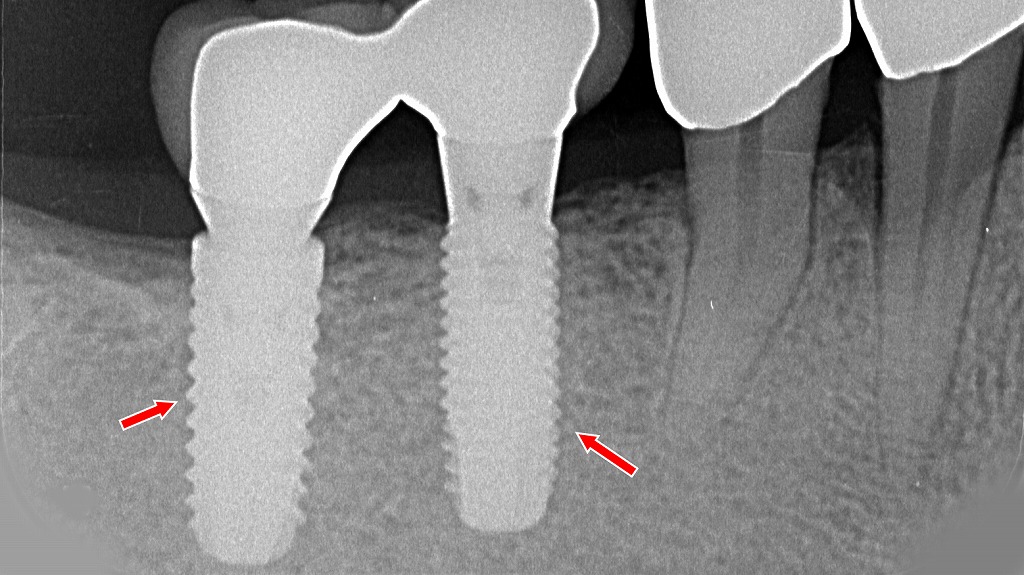

ブリッジを支える支台歯に、重度歯周病による歯槽骨吸収と歯の動揺が認められる症例です(赤矢印)。さらに、支台歯の一部には歯根破折が確認されており、これが痛みや違和感、噛んだときの不快症状の原因となっています。

ブリッジは複数の歯で力を支える治療法のため、歯周病が進行すると負担が集中し、炎症の悪化や歯根破折を引き起こすリスクが高まります。痛みが出た場合は、単なる噛み合わせの問題だけでなく、歯周組織や歯根の状態を含めた精密な診断が重要です。

6番・7番相当部に2本のインプラントを埋入し、上部構造として強度・耐久性に優れたフルジルコニアクラウンを装着した症例です。口腔内写真では天然歯と調和した形態と色調が得られており、咬合面形態も適切に付与されています。X線写真では、両インプラントフィクスチャーが良好な骨支持を得ており、スレッド周囲に明らかな骨吸収は認められません。上部構造は連結設計とすることで咬合力が分散され、長期的な安定性が期待される状態です。